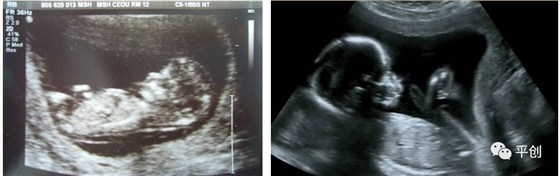

更準(zhǔn)確的醫(yī)學(xué)診斷,來自B超檢查結(jié)果的輔助,準(zhǔn)確的B超檢查結(jié)果,來自B超醫(yī)生看到的B超圖像,清晰的B超成像,來自好的耦合劑。所以說,好的耦合劑對B超的成像很重要。

而影響B(tài)超檢查成像的因素有兩點(diǎn),一是來自好的探頭,二是來自優(yōu)質(zhì)的耦合劑。如果這兩個產(chǎn)品其中有一個質(zhì)量不過關(guān),即對B超成像有一定程度的影響,可能會有成像不清楚,醫(yī)生無法準(zhǔn)確判斷所檢查器官的實(shí)際病變,嚴(yán)重的有可能度至醫(yī)生誤診的后果。

另外,有的廠家的耦合劑濃度太高,或是太稀,涂在檢查部位上,馬上就有一部分水流出,讓患者感到很不舒服,而過稀的耦合劑會減低其偶合性,過濃的耦合劑難以展開涂抺,或涂抺不均勻,影響探頭在檢查部位的滑動,這兩種情況都會減低B超中的耦合性,影響B(tài)超成像的清晰度,從而影響醫(yī)生看到的結(jié)果而給出錯誤的判斷,甚至間接的引發(fā)了醫(yī)療事故,嚴(yán)重地影響了醫(yī)院的專業(yè)度和信服力。這些都是醫(yī)生和醫(yī)院及患者都不希望發(fā)生的。

所生產(chǎn)出來的耦合劑無雜質(zhì)、透明度高、不易干,不化水,易偶合、易擦凈,透聲性超過國家標(biāo)準(zhǔn)的50%(數(shù)據(jù)通過國家指定的第三方檢測機(jī)構(gòu)檢測結(jié)果所得),完全地解決了成像不清晰的難題。

安創(chuàng)安必潔耦合劑已經(jīng)在廣東省人民醫(yī)院、南方醫(yī)院、中山大學(xué)附屬第一醫(yī)院等全國各三甲醫(yī)院使用,并得到了各醫(yī)院的一致認(rèn)可,解決了其它品牌耦合劑的偶合性差、透聲功能低,成像不清晰的問題,減少了B超結(jié)果誤診的機(jī)率,同時也解決了短期內(nèi)要多次尋找耦合劑品牌的煩惱,所以得到了各合作醫(yī)院的聯(lián)合推薦使用:“好的耦合劑,選用安創(chuàng)安必潔消毒耦合劑”。